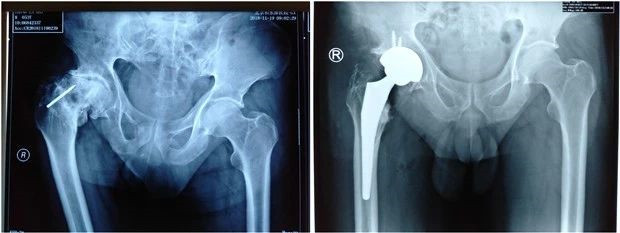

髋关节THA术前与术后